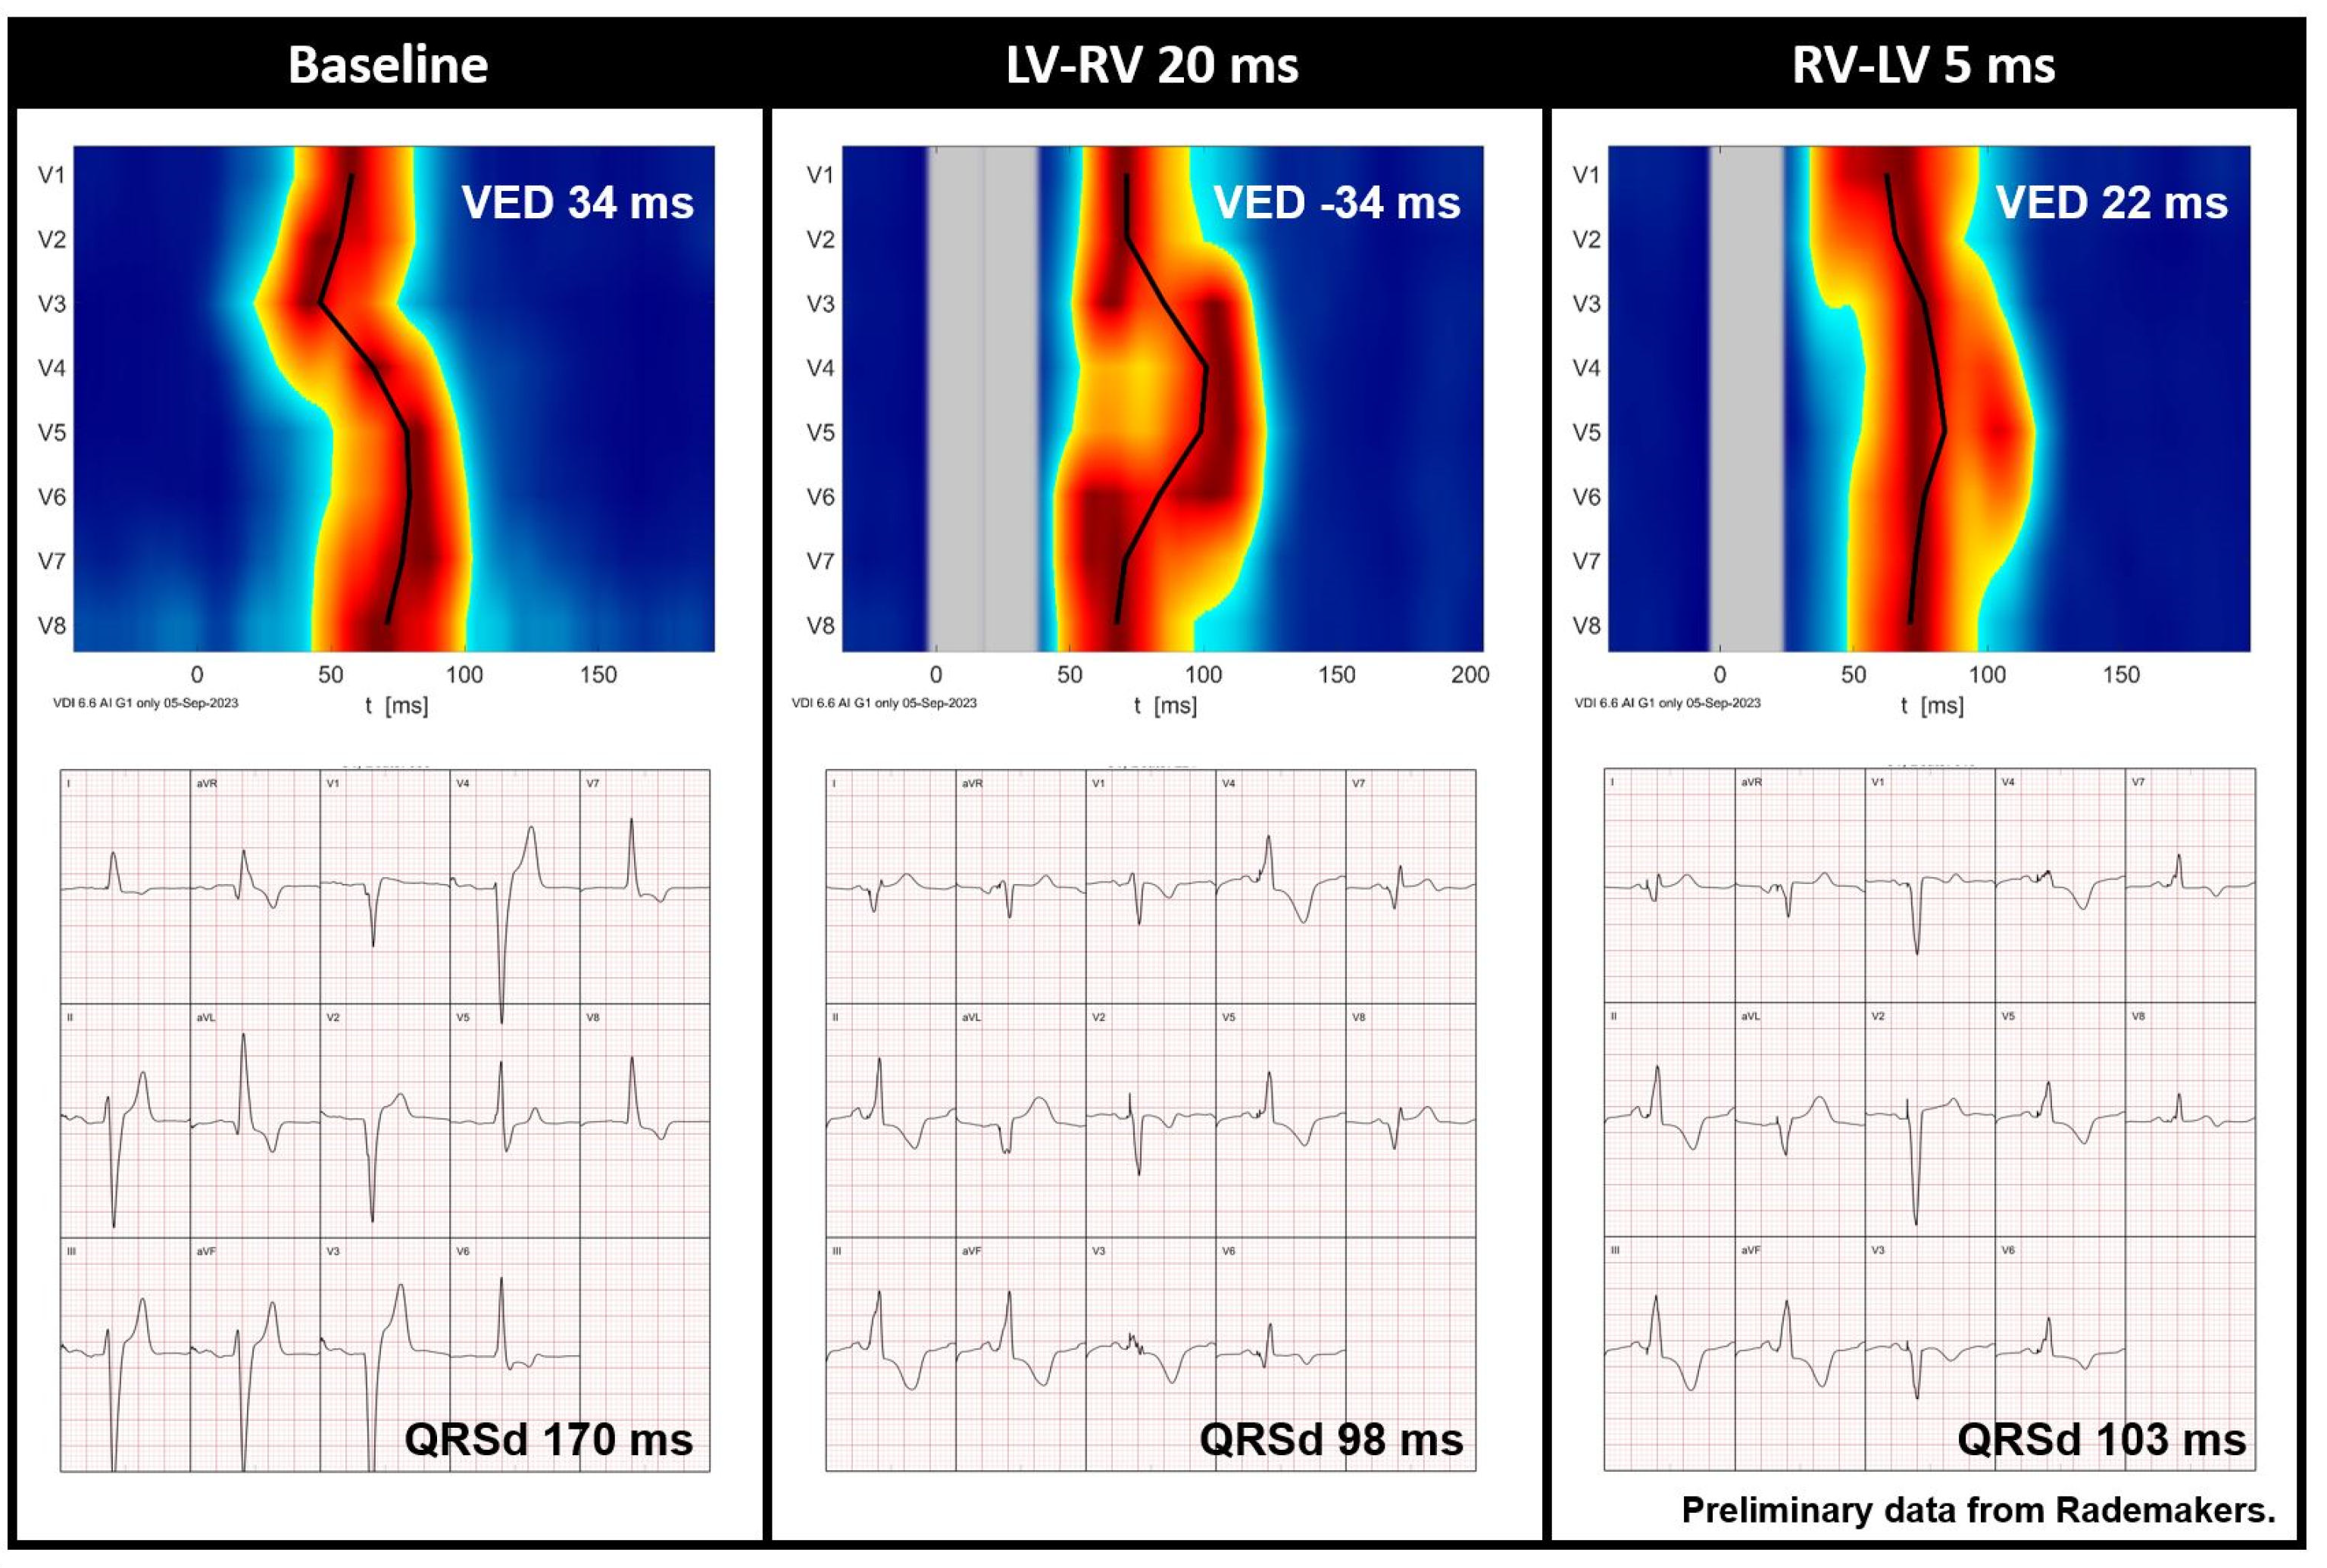

Figure 6.

Preliminary data from Rademakers et al. demonstrating the UHF-ECG activation map and averaged ECG of a CRT recipient before implantation and during various VV interval settings. Red indicates the time (horizontal axis) and location (vertical axis) when most myocardial cells are activated simultaneously. It is noteworthy that QRS duration is relatively short during an LV-RV of 20 ms, whereas the UHF-ECG reveals dyssynchronous activation. In contrast, an RV-LV of 5 ms results in more synchronous activation (ventricular electrical delay, 22 ms). Abbreviations: QRSd = QRS duration, VED = ventricular electrical delay.